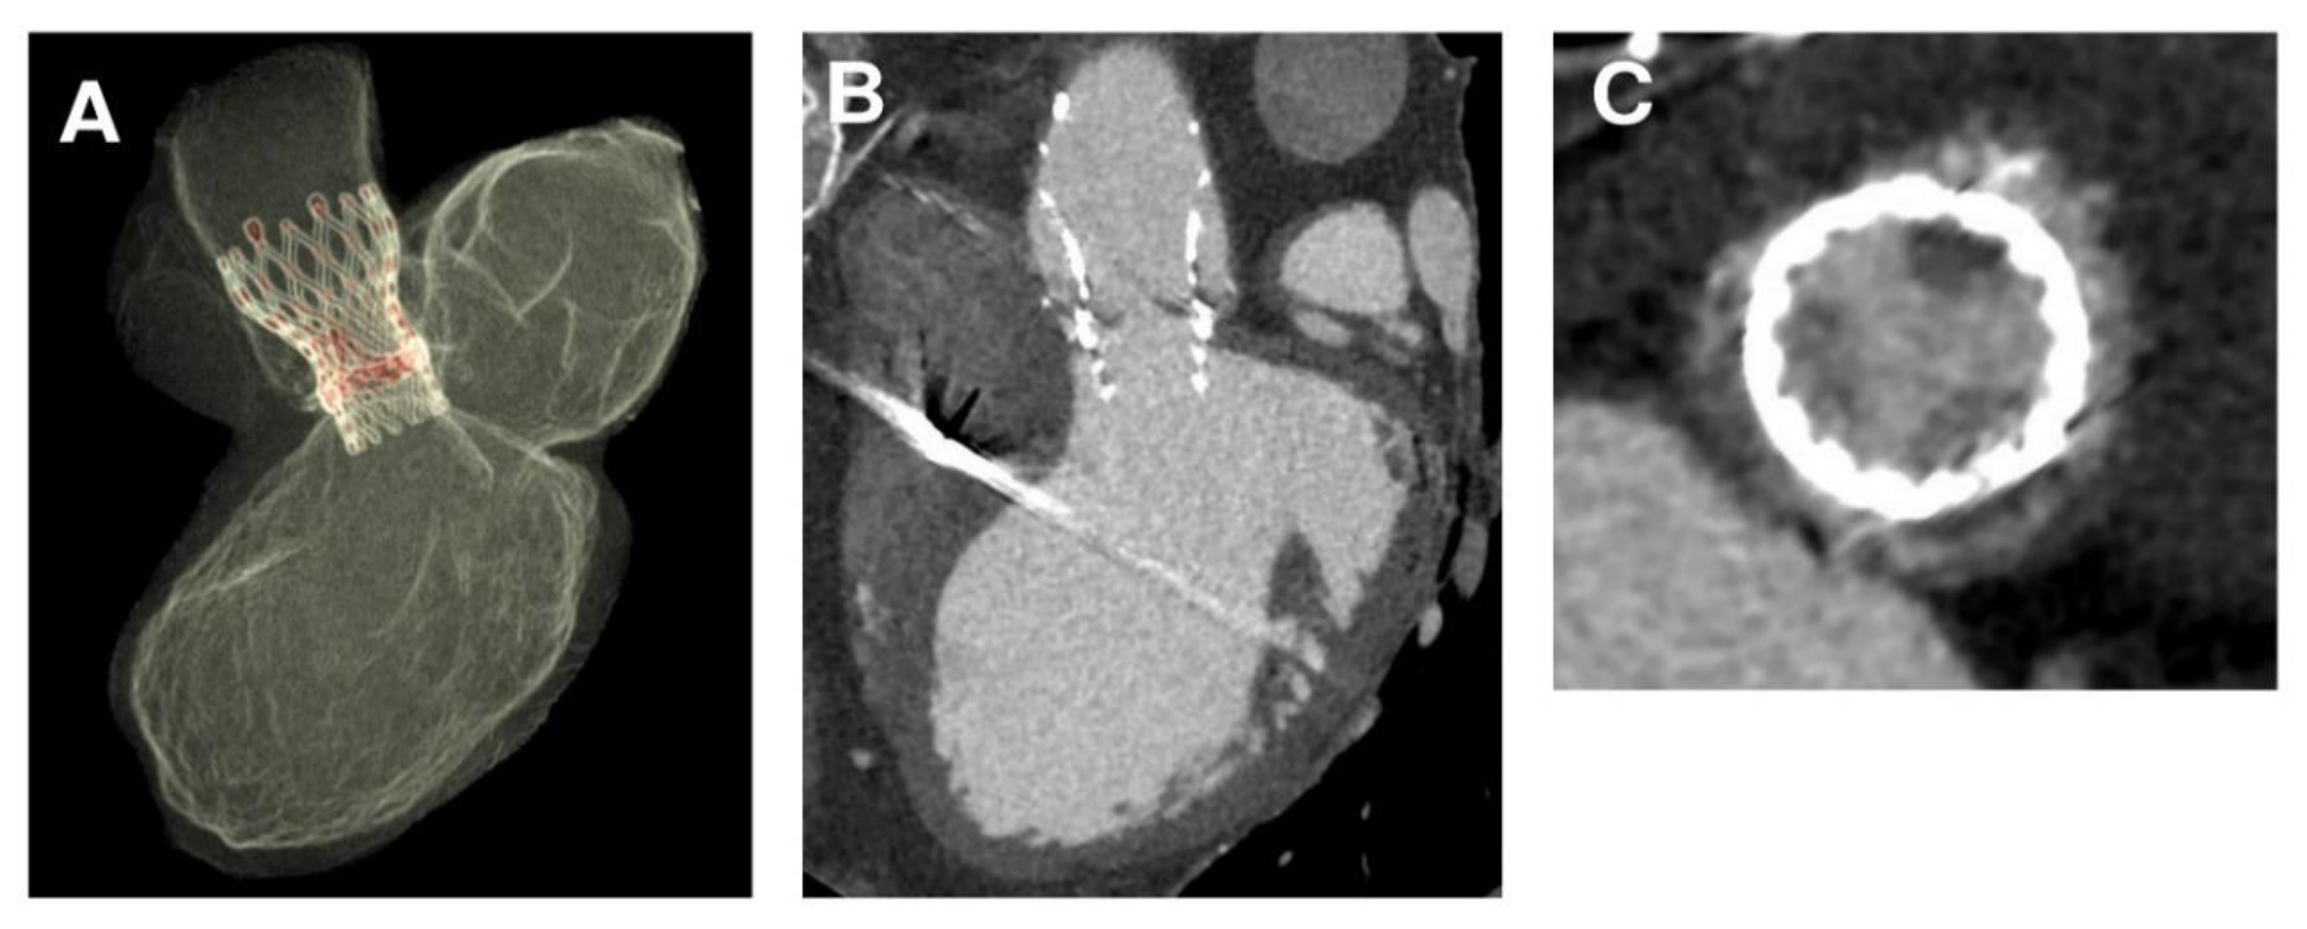

3.1. Phase 1—Processing Medical Images

3.2. Phase 2—Simulation of the Entire Clinical Procedure after Analysis of the Acquired Data